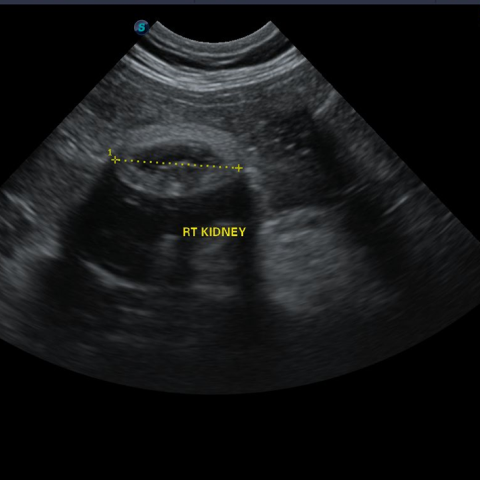

½ÅÀåÇ÷¾×°Ë»ç(BUN, CREA, P, ÀüÇØÁú), SDMA(½ÅÀå ¿©°úÀ² °Ë»ç), Ç÷¾Ð, ¿ä °Ë»ç, º¹ºÎ ÃÊÀ½ÆÄ °Ë»ç¸¦ ÅëÇØ ½ÅÀ庴 ´Ü°è¸¦ Áø´ÜÇÕ´Ï´Ù.

µ¶¼º¹°ÁúÀ» ¸Ô¾úÀ» ¶§, ±¸Å䳪 ¼³»ç°¡ Áö¼ÓµÉ ¶§, ´ÙÀ½ ´Ù´¢ °¡ ÀÇ½ÉµÉ ¶§, °Ç°°ËÁø ÇÒ ¶§, ¸¶Ãë Àü °Ë»ç ½Ã Á¤¹Ð°Ë»ç·Î ½ÅÀå°Ë»ç¸¦ ÁøÇàÇÕ´Ï´Ù.